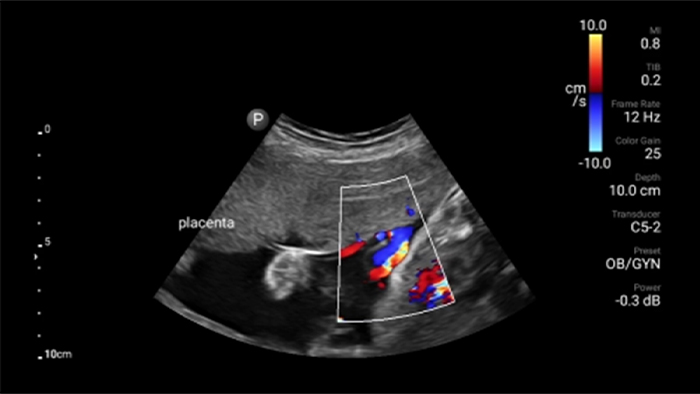

• 4 to 1 MHz extended operating frequency range • 2D, color Doppler, M-mode, advanced XRES and multivariate harmonic imaging • High-resolution imaging for abdominal and cardiac applications: Cardiac, OB/GYN, Lung, Abdomen and FAST imaging preset optimizations Lumify aids life-saving technology in prehospital setting